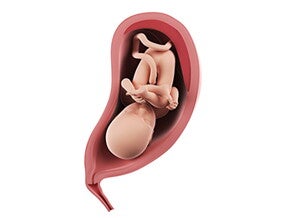

מה קורה לעובר?

הערכת המשקל המשוערת של העובר היא בסביבות 2 קילוגרמים. זה רק אומדן, והמשקל משתנה בין עוברים זכרים לעוברים ממין נקבה (זכרים גדולים יותר) ובהתאם לנתונים הגנטיים. העיניים של העובר שלך כבר פקוחות כשהוא ער ועצומות כשהוא ישן. תאי המערכת החיסונית נוצרים בגופו. בשלב זה העובר ערני ואף מקשיב לצלילים סביבו.